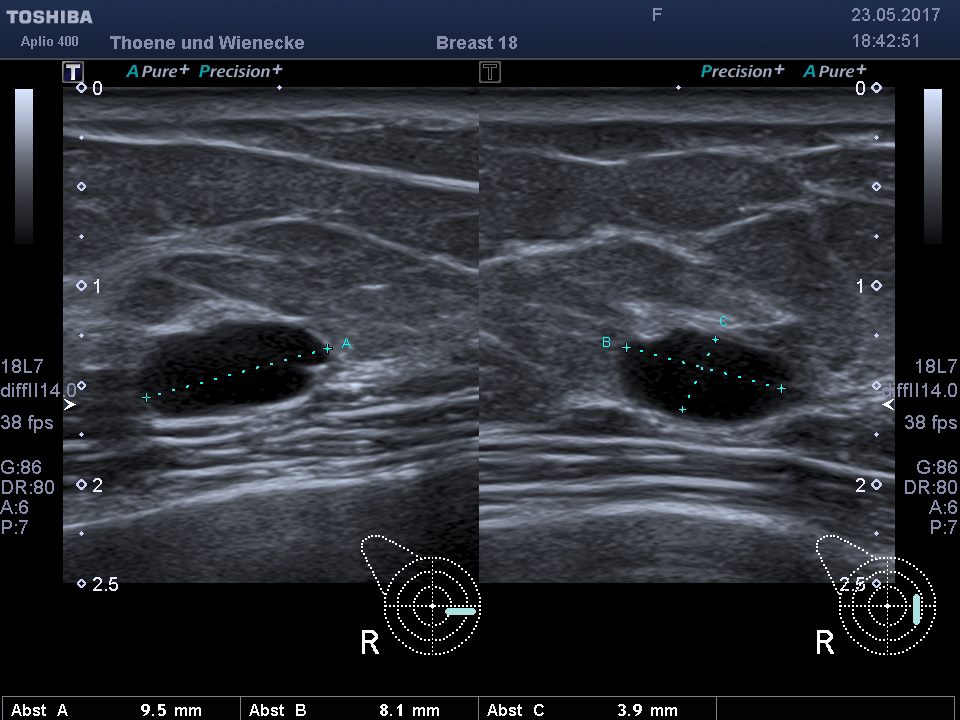

Der Ultraschall ist eine Untersuchung ohne Strahlenbelastung. In unsrer Praxis werden hochauflösende Ultraschallköpfe verwendet, die eine hohe Genauigkeit und sehr gute Auflösung ermöglichen. D.h. auch kleinste Veranderungen können schon gesehen werden. Mit der 3 D Sonographie können Veränderungen des Gewebes in ihrer Abgrenzung zum normalen umgebenden Gewebe besser beurteilt werden als nur mit der 2 D Methode. Bösartige Knoten bilden Ausläufer in das umgebende Gewebe, die wie kleine Strahlen einwachsen. Diese Phämomene können mit der 3 D Sonographie beurteilt werden, die Unterscheidung zwischen gutartigen und bösartigen Veränderungen wird genauer und die Rate an unnötigen Biopsien kann vermindert werden.